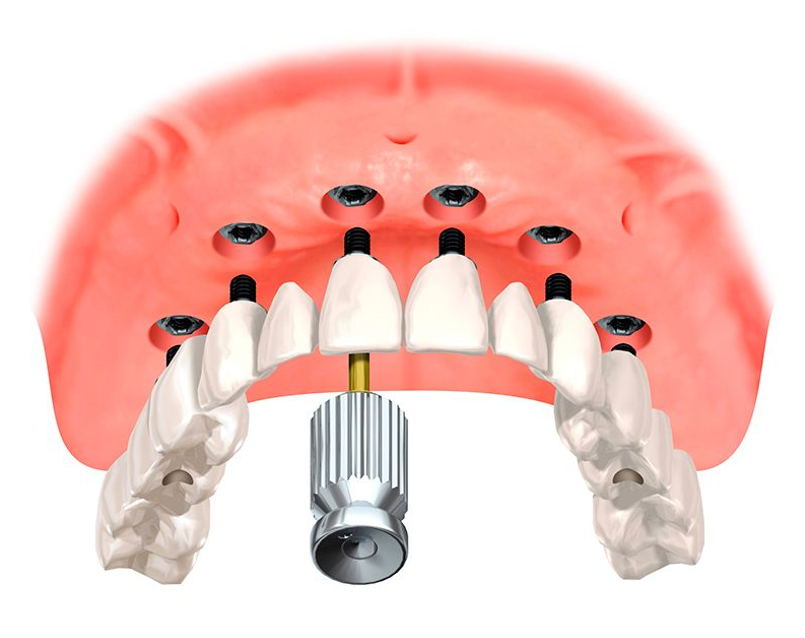

Пошаговое руководство по установке съёмного протеза на импланты